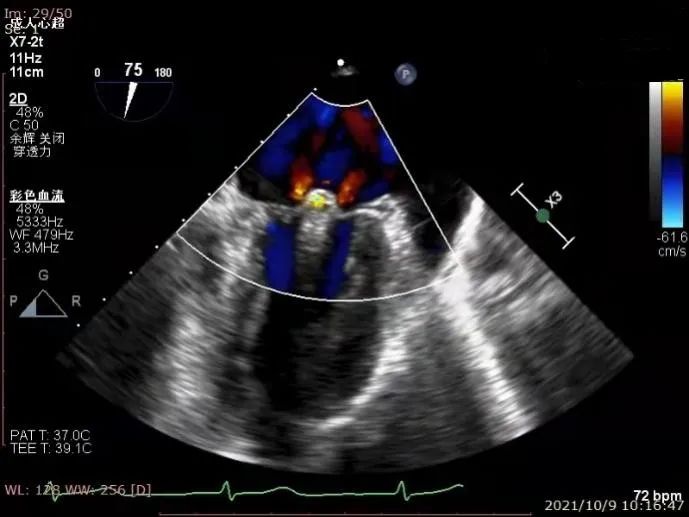

术后心超

患者全麻后,在超声和射线引导下器械经股静脉穿刺房间隔,通过输送系统送入患者左心房,顺利到达病变的二尖瓣区域。在经食道超声及DSA引导下,术者通过反复评估二尖瓣膜脱垂范围、抓捕位置、反流程度,精准夹合,成功植入一枚DragonFly瓣膜夹稳定脱垂瓣叶。患者术后反流从4+减少到1+,跨二尖瓣平均压差3mmHg,血流动力学改善明显,手术取得圆满成功。